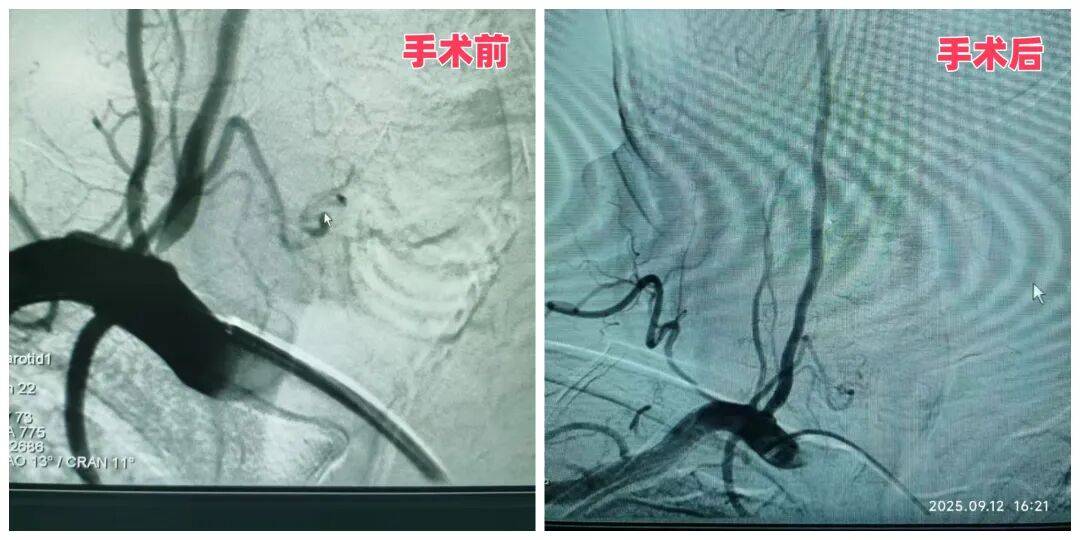

精準(zhǔn)介入,為李大哥“撐”起穩(wěn)定供血通道

57歲的李大哥半年內(nèi)因反復(fù)頭暈住院三次,出現(xiàn)兩次右側(cè)小腦急性梗死,經(jīng)檢查確診為“雙側(cè)椎動(dòng)脈起始段狹窄”,其中右側(cè)已達(dá)重度狹窄,隨時(shí)可能再次引發(fā)腦梗。神經(jīng)內(nèi)科二病區(qū)主任袁秀琴、主管醫(yī)生楊偉偉、護(hù)士長(zhǎng)馬曉玲結(jié)合患者的高血壓、糖尿病病史及既往腦梗情況,術(shù)前為患者進(jìn)行降壓、降糖治療,并制定了 “主動(dòng)脈弓 + 腦血管造影術(shù) + 右側(cè)椎動(dòng)脈支架植入” 的精準(zhǔn)治療方案。

手術(shù)中,醫(yī)生憑借豐富的介入經(jīng)驗(yàn),將支架精準(zhǔn)植入右側(cè)椎動(dòng)脈狹窄處,成功撐開狹窄血管。術(shù)后復(fù)查患者右椎動(dòng)脈供血恢復(fù)正常。這例手術(shù)的成功,標(biāo)志著科室在腦血管狹窄精準(zhǔn)治療領(lǐng)域的技術(shù)已趨于成熟,能為復(fù)雜病情患者提供安全有效的方案。